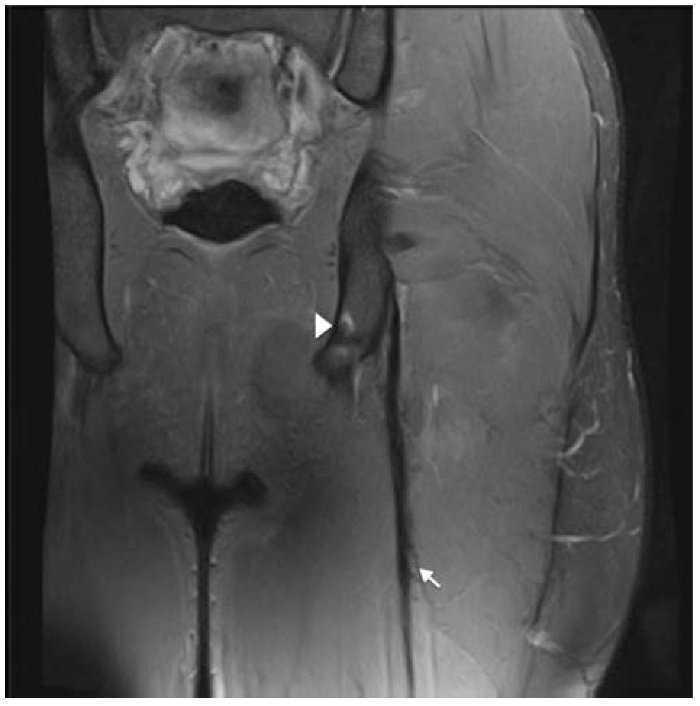

Figure 2 Coronal and axial T2 Fat-saturated images of the left hamstring show thickening and signal intensity changes of the free tendon (arrow), blurring contours and discontinuity that extent until proximal MTJ. There is mild distal retraction of the proximal MTJ. Semitendinosus muscle belly (ST), gluteus maximus (GM), semimembranosus tendon (arrowhead) and sciatic nerve (*).

Eighteen years old professional football player suffered the same kind of pain in the same kind of circumstances. Clinical signs were exactly similar than the previous acute hamstring strain described but the MRI exam showed different images (Figs. 3 and 4) because the injury was located in the free tendon of BF. The length of free-tendon was 8.5 cm and the injury was located at 6.5 cm from the ischial tuberosity. Due to the long time of recovery and a high reinjury rate, surgical treatment should be considered. Excision of the scar tissue, including the torn portion of the tendon was then performed and tension-free suturing of the belly remnant of the biceps femoris to the adjacent semitendinosus. In order to provide tension to the tendon and reinforcement with anchors in ischial tuberosity (Figs. 3 and 4).

Figure 4 Coronal T2 Fat-saturated image of left hamstring in post surgery follow-up, that show the metallic anchor in ischial tuberosity (arrowhead) and peritendinous sutures represented by magnetic susceptibility peritendinous artifacts (arrow).